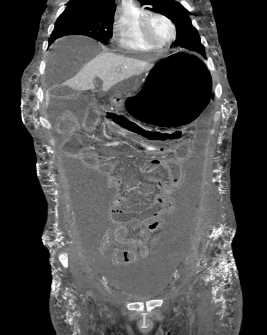

Another cutaneous manifestation noted in our patient is calcinosis cutis (Figure 4), which is simply the formation of calcium deposits in soft tissues. This finding is more commonly reported in cases of JDM rather than adult DM, with one study noting its prevalence in 43% of cases.9 The pathophysiology is multifactorial and poorly understood, but it is thought to be caused by a combination of chronic inflammation alongside genetic and environmental factors.10 In a study analyzing the risk factors associated with calcinosis in JDM, the overall incidence of calcinosis cutis was noted to be increased in patients with more severe disease manifestations or in those taking one or more immunomodulators.9 Subcutaneous calcinosis is therefore a sign of more advanced disease and indicates an overall poorer prognosis. Our patient presented with diffuse abdominal subcutaneous calcinosis with a distribution that extended into the lower chest, flanks and pelvic area (Figure 5). These underlying, severe calcium depositions formed an exoskeleton that is typically seen with treatment-resistant cases.11-12

Figure 5 Diffuse calcinosis cutis in the abdominal wall on CT abdomen/pelvis (coronal view and tissue window).